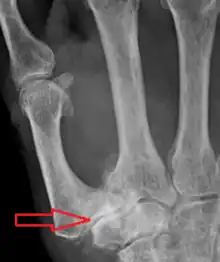

TMC OA is diagnosed based on symptoms and signs.[8] Radiographs can confirm the diagnosis and the severity of TMC OA. Other diagnoses in this region include scaphotrapezial trapezoid arthritis and first dorsal compartment tendinopathy (De Quervain syndrome) although these are usually easy to distinguish.

Classification

TMC OA severity was classified by Eaton and Littler which can be simplified as follows:[21][22]

Stage 1:

- slight widening of the joint space

- < 1/3 subluxation of the joint (in any projection)

Stage 2:

- Osteophytes, < 2 mm in diameter, are present. (usually adjacent to the volar or dorsal facets of the trapezium)

Stage 3:

- Osteophytes, > 2 mm in diameter, are present (usually adjacent to the volar and dorsal facets of the trapezium)

- Slight joint space narrowing

Stage 4:

- Narrow joint space

- Concomitant scaphotrapezial arthritis

A simpler classification is no arthritis, some arthritis, and severe arthritis.[23] This simpler classification system omits the potentially contradictory details of the Eaton/Littler classification and keeps scaphotrapezial arthrosis separate.